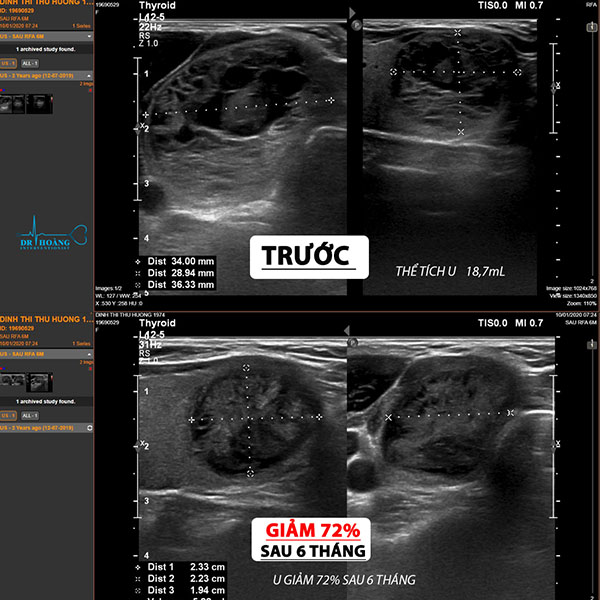

Giảm nhanh thể tích bướu giáp

Chị Thu Hương (1974) được chỉ định đốt sóng cao tần khối u lành tuyến giáp khá lớn với thể tích 18,7ml. Khối u gây biến dạng vùng cổ với khối lồi to gây mất thẩm mỹ và ảnh hưởng nhiều đến sức khỏe, cuộc sống. Sau đốt sóng RFA, chị Hương không thấy đau và về nhà ăn uống sinh hoạt, làm việc bình thường.

Kết quả tái khám sau 6 tháng cho thấy kết quả tích cực khi giảm hơn 72% thể tích bướu giáp. Đặc biệt, sức khỏe cải thiện rõ ràng, vùng lồi ở cổ biến mất trở về bình thường.